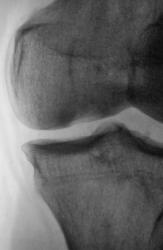

А вот примерно так выглядит это ложе на КТ, пока оно ещё не опустело (ложе в медиальном мыщелке помечено стрелками). Б-нь Кенига.